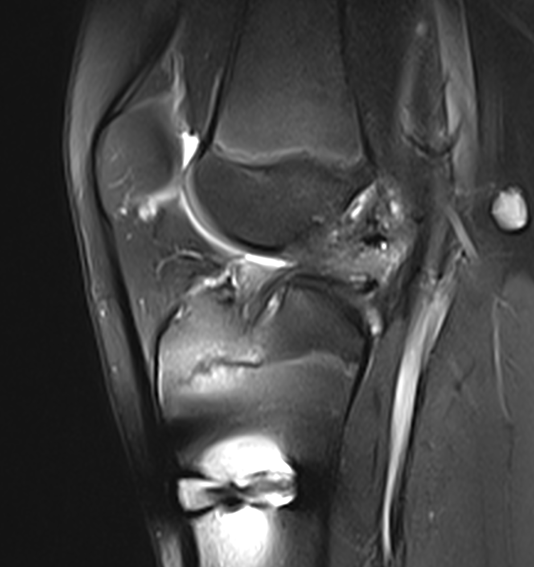

All patients (3 female, 7 male) presented with recurrent knee instability after primary ACLR and after typical rotation-valgus trauma during sports activities. Patients were examined clinically by the first author, scheduled for magnetic resonance imaging to verify the injury and then consented for ACLR by using an ipsilateral QT autograft. None of the patients had an injury of the anterior lateral structures or relevant collateral ligament injuries that needed surgical repair. Six patients had meniscus injury and three had cartilage degeneration or defects. All patients underwent primary ACLR (7 HT and 3 patellar tendon autografts, mean 4.7 years ago (3.4-10.7)). Postoperatively, patients were followed-up for a minimum of twelve months and visited the office every two months for clinical examination. During the twelve months follow-up period, all ten patients reported discomfort and recurrent subjective instability during sports or every day activities. None of the patients reported adequate trauma as possible cause for a graft re-rupture and recurrent instability. As a consequence, all ten patients underwent MRI examination to assess graft integrity (Figures 1). In all ten patients, the MRI scans confirmed complete graft resorption (Figures 1). Arthroscopic evaluation further verified this finding, showing an empty notch with only small tibial remnants in the affected patients (Figure 2). As a result, eight patients underwent revision ACLR by using allografts. Two patients refused to undergo further surgical procedures and chose conservative treatment.

Figure 1.16-year old male patient at follow-up MRI five months after QT autograft ACLR showing complete graft resorption and missing graft signal.